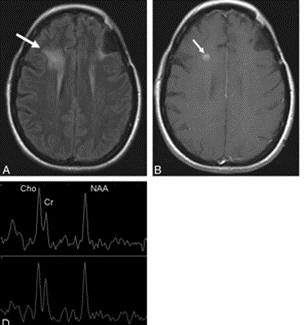

4.4. Cộng hưởng từ phổ (MRS- Magnetic Resonance Spectroscopy)

Hình 6: Hình ảnh FLAIR (A) và hình ảnh T1 sau tiêm thuốc đối quang từ (B) thu được 8 tháng sau khi phẫu thuật, xạ trị và hóa trị một khối u thần kinh đệm anaplastic ở thùy trán trái cho thấy một vùng tăng tín hiệu mới trên FLAIR (mũi tên, A) và một nốt tăng tín hiệu (mũi tên, B) ở thùy trán phải trong thể tích được chiếu xạ, nghi ngờ bị tổn thương do xạ trị. D, Hình ảnh cộng hưởng từ phổ cho thấy cường độ tín hiệu NAA giảm nhẹ và Cho tăng ở cả hai bên, gợi ý tổn thương do xạ trị.

Cộng hưởng từ phổ là một kỹ thuật chụp ảnh không giải phẫu xác định sự hiện diện và nồng độ của nhiều chất chuyển hóa khác nhau trong một vùng não đã chọn trước đó. Trong não bình thường, các chất chuyển hóa như N-acetyl aspartate (NAA- một dấu hiệu của chức năng tế bào thần kinh bình thường) và choline (Cho- thành phần của màng tế bào) là các đỉnh chiếm ưu thế trong đồ thị quang phổ. Do đó, sự thay đổi trong thành phần chuyển hóa trong não (tổn thương tế bào thần kinh, tính dẻo của tế bào thần kinh, v.v.) sẽ làm thay đổi nồng độ tương đối của các hợp chất đó. MRS cũng có thể phát hiện lipid (Lip), biểu thị tổn thương/hoại tử. Tỷ lệ đỉnh MRS có thể hỗ trợ chẩn đoán chính xác và phân biệt hoại tử não do bức xạ với tiến triển khối u.Tỷ lệ NAA/Creatinin (Cr; một dấu hiệu của dự trữ năng lượng tế bào) cao hơn ở hoại tử não do bức xạ so với tiến triển khối u, trong khi tỷ lệ Cho/NAA và Cho/Cr cao hơn ở khối u tái phát so với tổn thương hoại tử. Đáng chú ý là MRS đòi hỏi thời gian quét dài vì cần phải chụp nhiều lần để đánh giá chính xác và là một phương thức chẩn đoán tốn kém. Các dấu hiệu chuyển hóa MRS mới như 2-hydroxyglutarate đang được nghiên cứu chuyên sâu; tuy nhiên, ứng dụng lâm sàng của nó vẫn còn hạn chế   4.5. Chụp cắt lớp phát xạ positron (PET-CT- Positron Emission Tomography and Computed Tomography)